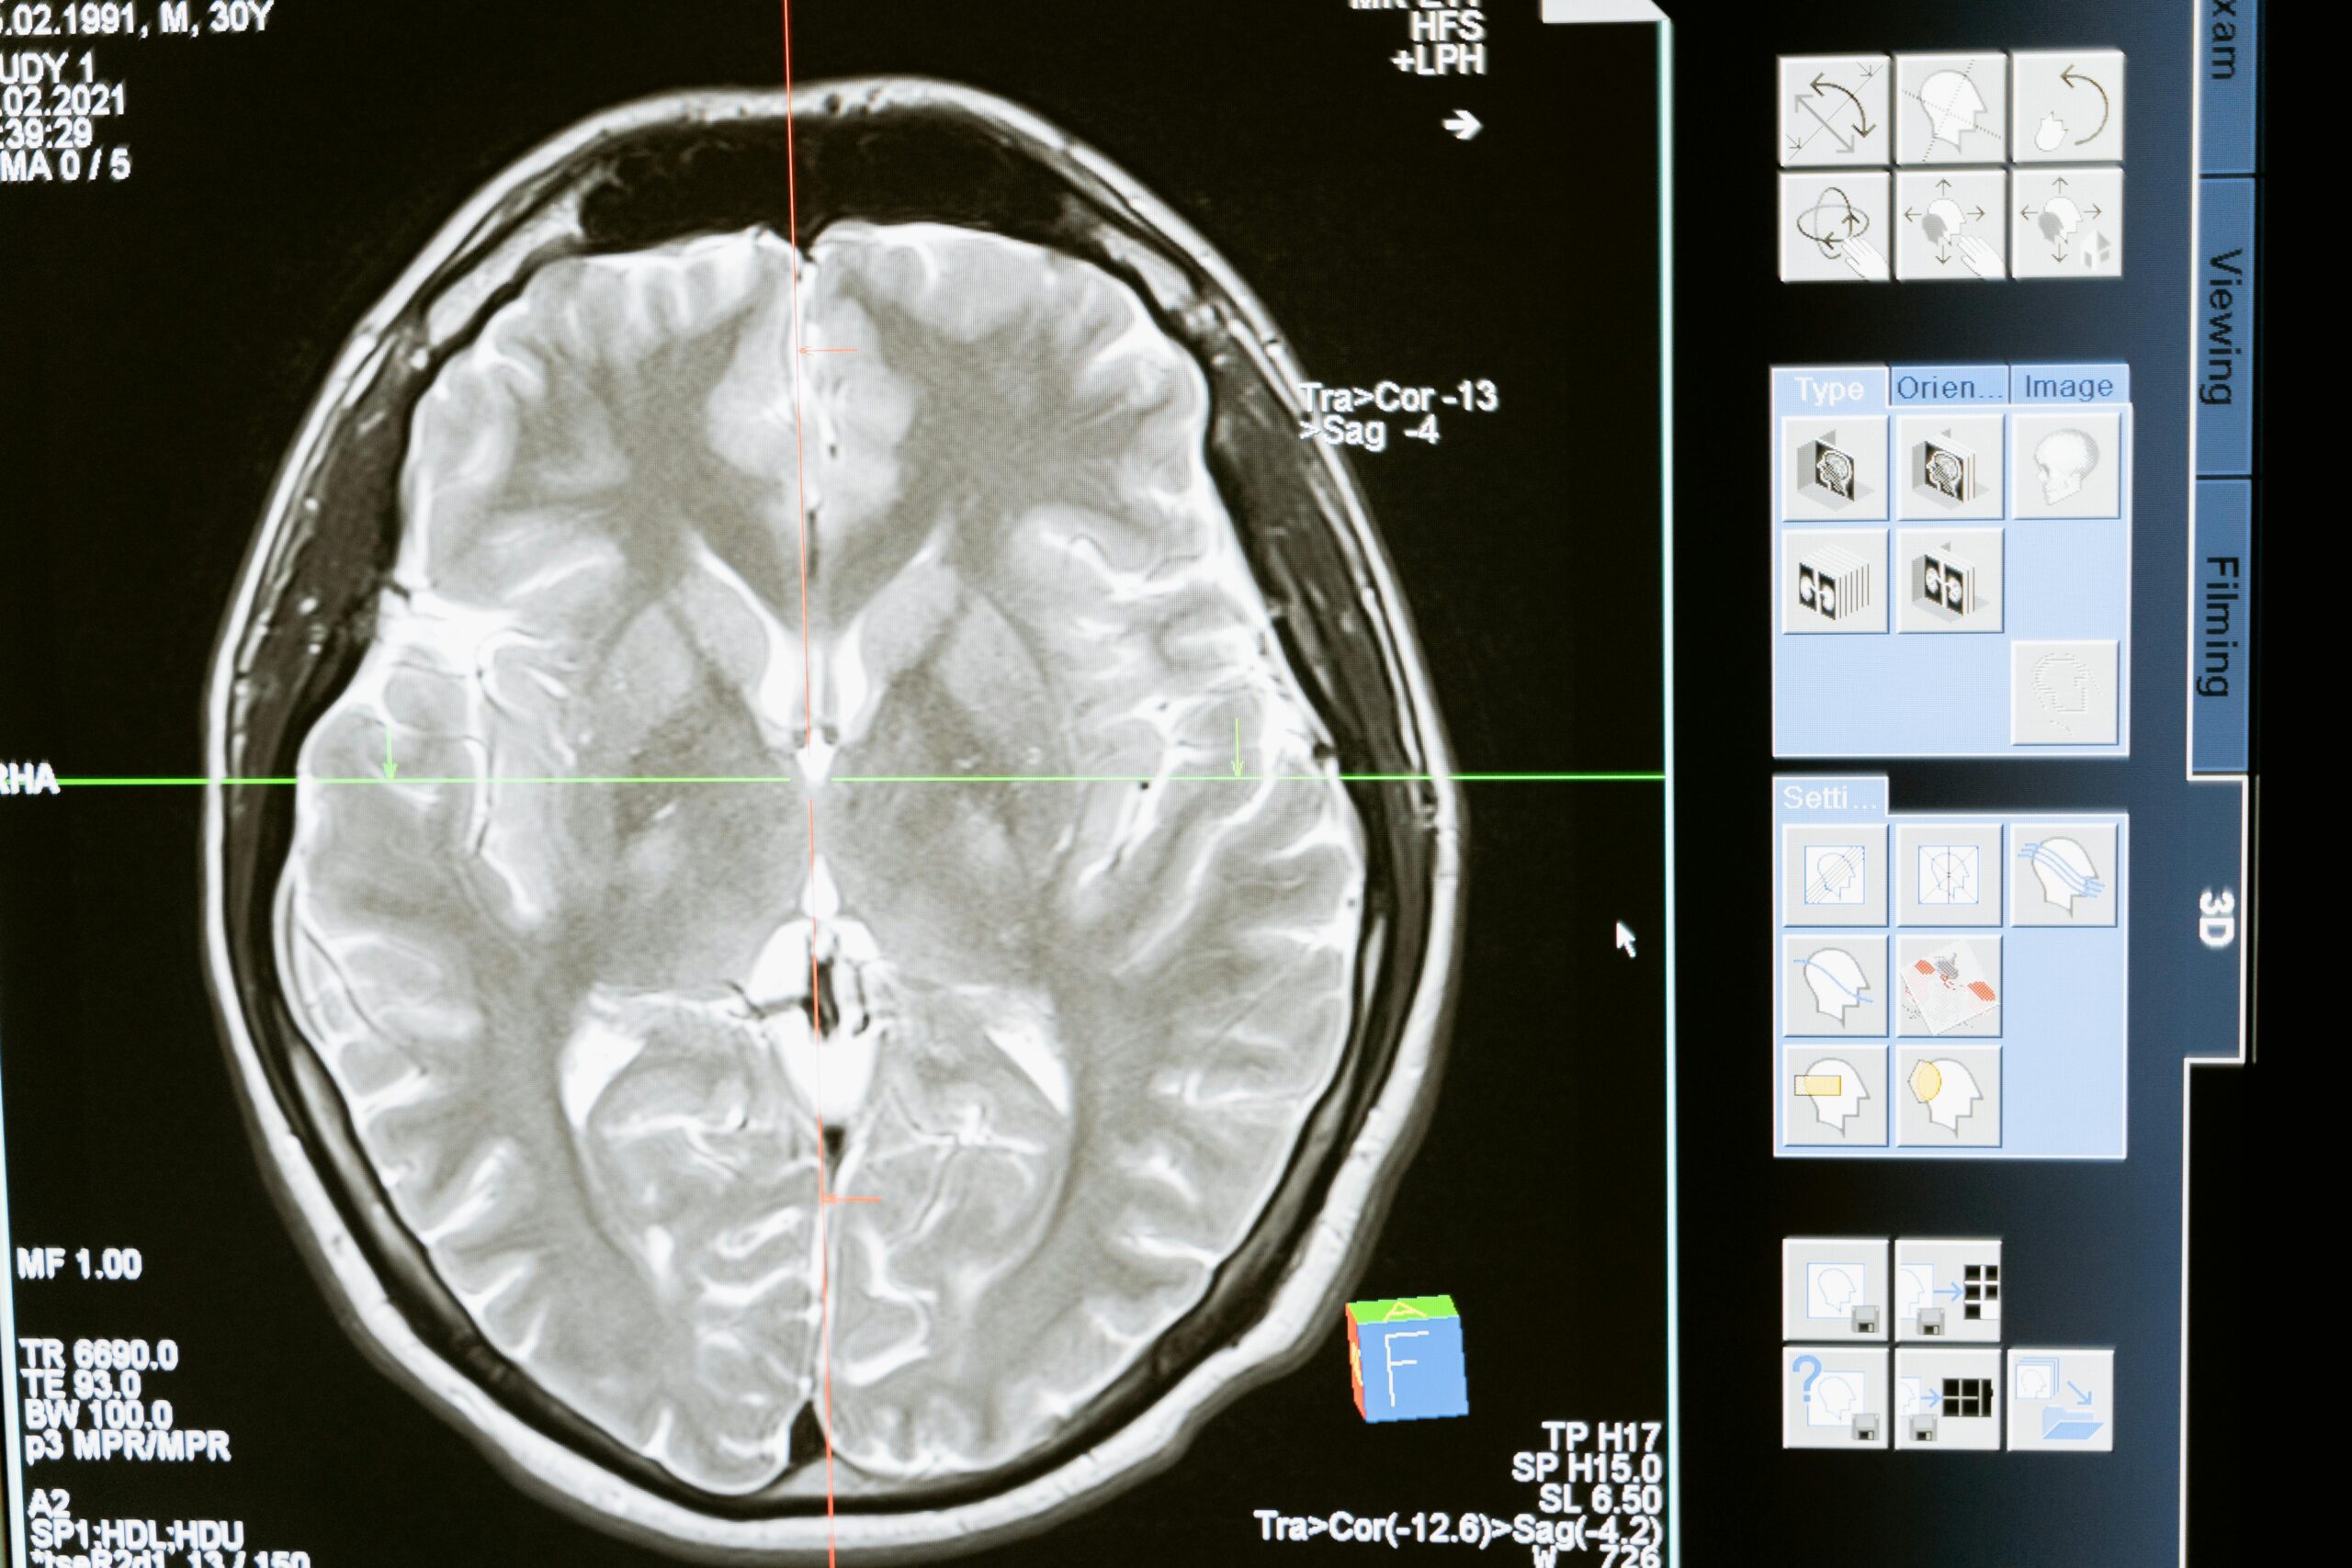

Rachael Seidler, a professor at the University of Florida, led the study published in Proceedings of the National Academy of Sciences. The team examined brain scans of 26 astronauts who lived on the International Space Station.

On Earth, gravity gently pulls the brain down inside our heads. In space, that anchor disappears. The brain floats higher, and fluids move toward the skull, causing the brain to stretch and compress in different directions.

The changes are small but measurable. In astronauts who spent up to a year in space, the motor cortex — the part that controls movement — shifted upward by about 2.5mm. This shift can cause temporary balance and coordination problems when astronauts return home.

Earlier studies also found that fluid-filled spaces inside the brain grow larger. For most astronauts, the brain returns to normal within six months back on Earth. But the recovery is not instant.